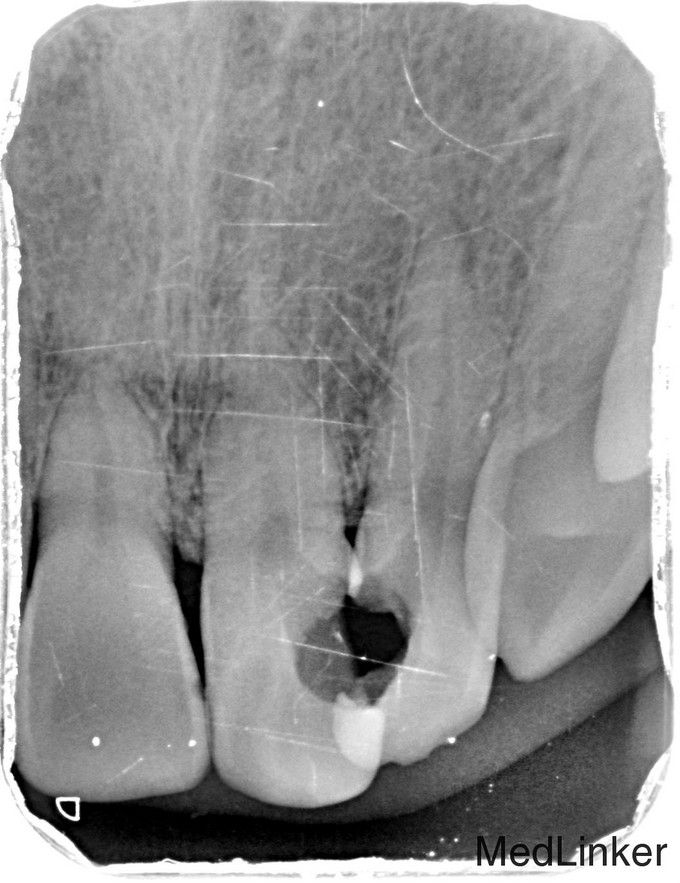

临床检查:21,22之间邻面龋坏,探(++),冷(++),叩(-),松动度(-),可探及穿髓点,无窦道,牙周红肿。 辅助检查:X线示21,22龋坏累积髓腔,根尖周牙周膜增宽。

诊断:21,22牙髓炎 治疗:经患者知情同意后,21,22局麻去腐,开髓拔髓寻找根管口,建立直线通路,扩通根管,确定工作长度。S3/EDTA凝胶镍钛器械,低浓度次氯酸钠冲洗根管,预备至30/06,试主尖X线示恰充,试干根管,导AH-PLUS糊剂,VDW热压胶垂直加压根充,术后见根管恰充,垫底树脂充填。调合术后24小时抛光。